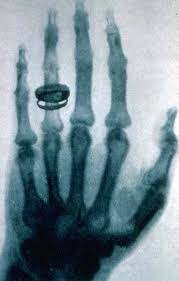

• La radiografía

La radiografía

El descubrimiento llegó el 8 de noviembre de 1895. Mientras estudiaba el poder de penetración de los rayos catódicos, Röntgen observó que una placa de cartón cubierta de cristales de platino-cianuro de bario emitía una fluorescencia, que desaparecía al desconectar de la corriente.